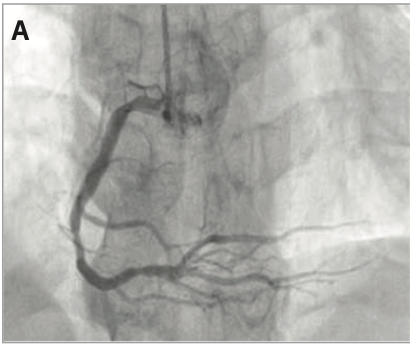

A 58-year-old male patient, a heavy smoker who presented to an outside hospital as a case of anterior ST-elevation myocardial infarction, was referred to our hospital for rescue percutaneous coronary intervention after failed thrombolytic therapy. Coronary angiography and successful rescue PCI were performed, but while trying to reopen a diagonal branch that was occluded after stenting the left anterior descending coronary artery, an unexpected complication occurred, which was managed successfully. This case reveals the importance of proper procedural planning, as well as the importance of imaging-guided coronary intervention specifically, should complications occur.